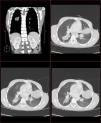

Varón de 8 años, procedente del medio rural marroquí, con accesos de tos crónica, productiva y hemoptisis ocasional de 6 meses de evolución. Afebril y sin otra sintomatología, presenta buen estado general, ausencia de dificultad respiratoria y buena ventilación pulmonar generalizada. Se desconocen tratamientos y estudios previos. En la radiografía de tórax (PA y lateral) (figs. 1 y 2) se aprecia condensación homogénea redondeada de contornos definidos, borrando silueta cardiaca en língula. Sin broncograma aéreo asociado. Perfil general y reactantes de fase aguda, normales. Leucocitos 4.400/ml3. Serologías de neumonía y Mantoux, negativos. Plantea diagnóstico diferencial con malformación pulmonar congénita (quiste broncógeno) y, considerando la procedencia del paciente, quiste hidatídico1. Se solicita TC torácica y serología a Echinococcus granulosus. Se evidencian en la ventana pulmonar (fig. 3) dos masas ovoideas bien definidas, con hipoatenuación central y sin participación pleural. La primera, de 32mm de diámetro (segmento 6 de LID), contacta con cisura mayor. La segunda era de 44mm, en la língula (segmento 4). Resto del parénquima pulmonar, sin otras masas ni nódulos. Mediastino sin adenopatías. La IgE específica a E. granulosus (8,38 KU/l), confirmada mediante hemaglutinación a hidatidosis2 (1/10.240), sugiere que las masas sean quistes hidatídicos. Ecografía abdominal sin afectación hepática. Se traslada al centro de referencia de cirugía infantil para tratamiento quirúrgico y confirmación anatomopatológica.